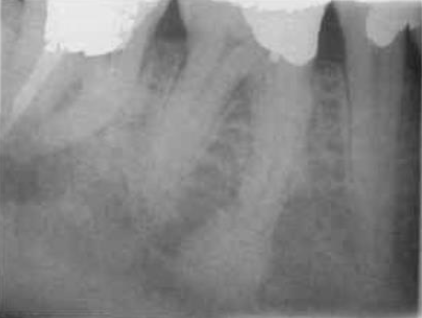

cancellous bone

the bony trabeculae have a coarser pattern and run horizontally in MN

compare with the finer lace-like pattern in MX

mandibular canal

aka: inferior dental canal

runs from the mandibular foramen in the ramus to the mental foramen

seen as a radiolucent band and may lie in close association with the apices of molar and 2nd premolar teeth

mental foramen

located below and distal to the apex of the 1st premolar

may be mistaken for a pathological lesion when it appears close to the apex of one of the premolars, which is due to the angle at which the radiograph is taken